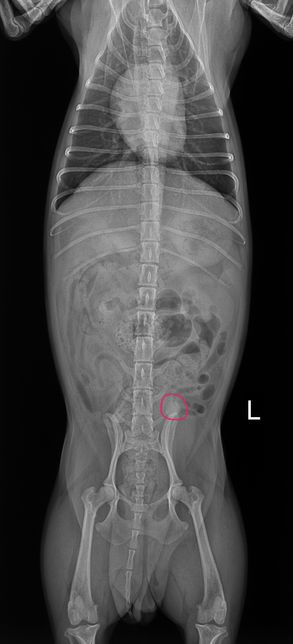

- 반려동물 건강반려동물Q. 강아지 엑스레이 사진 좀 봐주실 수 있는 분8살 암컷 강아지이고 어제 유선종양이랑 중성화 수술했는데 수술 전에 찍은 엑스레이에서 궁금한 점이 생겨 물어봅니다 혹시 엑스레이 상에서 제가 빨간색으로 동그라미 친 부분이 뭔 지 알 수 있을까요? 정확하게능 아니더라도 가늠이라던지 한번만 봐주세요..

- 반려동물 건강반려동물Q. 강아지 엑스레이 사진 좀 봐주세요ㅠㅠ강아지 엑스레이 찍었는데 빨간색 동그라미 친게 종양일까요? 유선종양 수술했는데 저 액스레이에 하얀게 뭔지 설명을 못 들었네요 아시는 분 계신가요?